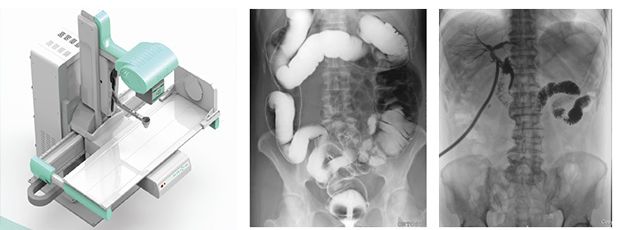

动态DRhttp://www.pl999.com/class.php?anclss=1&nclass=406既可做DR检查又可做穿透,其精细诊断大大降低误诊漏诊率;还可大幅面实时成像并具有及时保存证据,实现动态影像实时回放功能,有效避免普通DR拍片时病灶易被掩盖的缺陷。

普利德医疗器械厂家作为全球极好的数字影像设备供应商,专注于DR系列产品的技术jtgbosdwl创新,在全国范围内率先推出动态DR。以其“一机多用”集常规拍片、胃肠、透shi、造影于一体的多功能作用深受放射科临床医生的钟意。动态DR真正意义上实现临床病灶的快速定位和精细诊断,大幅提高医院的工作效率,是放射临床行家的得力助手。

医学影像技术在近百年间不断发展,尤其在近期更是发展迅猛,现如今新一代多功能动态DR成为行业高精尖技术引领下的潮流趋势。动态DR真正实现以用户需求为导向,以领先技术为保障,其“一台机器,多种用途”必然成为医院放射临床诊断的首要之选。

数字影像设备——新一代多功能动态DR优势